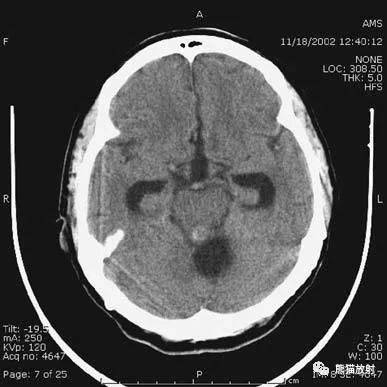

2、应注意的常见伪影

射线硬化伪影(Beam-hardening artefact):常见于颅脑基底部及后颅窝。

容积平均伪影(Volume-averaging artifact):层厚较大时,可导致血液密度表现,在脑基底部较典型,易发生在眼眶上方额叶。本例表现:四脑室囊性病变导致梗阻性脑积水。